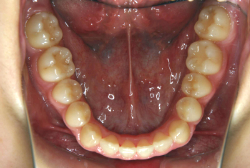

混合歯列期から治療開始した側方拡大による非抜歯症例

「配列の凸凹を治したい」という主訴で来院したケースです。診断の結果、永久歯がすべて生えそろうと、かなり厳しい叢生(歯並びの凸凹のことです)になる可能性が高いと判明しました。原因としては特に上の顎の骨が小さいため、歯を収容する容量不足になっていると診断しました。このケースの場合は、成長発育期に治療開始しますので、顎の骨を土台ごと大きくすることが可能です。

そこで、まず急速拡大装置を使用して上顎骨の拡大を行い、上顎骨の容量が拡大したことを確認後、マルチブラケット装置を使って全体の修正をする、と言う二段階の作戦をとることになりました。

この時期に使う急速拡大装置は、適切な診断に基づいて正しく使用することで確実に骨を大きくすることができます。拡大することで隙間が確保できるので、永久歯の抜歯を避けることができます。

急速拡大装置を1日1回装置の中央にある拡大ネジを、ご自身で回して頂くことで25日間くらいかけて、6mmほど拡大しました。拡大後は、上顎の前歯の隙間が広がっていることがお分かりいただけると思うのですが、土台の骨ごと広がるのでこのような隙間ができます。その後1年半くらいマルチブラケット装置を使用して、全体の修正を行いました。

結局、歯の本数を減らすことなく、すべてご自分の歯を残して正しい配列にすることができました。このケースの場合、2009年10月より拡大と経過観察を行い、2012年3月より1年2ヶ月マルチブラケット装置を装着、2013年5月に治療を終了しました。2段階で行う治療としては短期間で終了しているケースと思います。